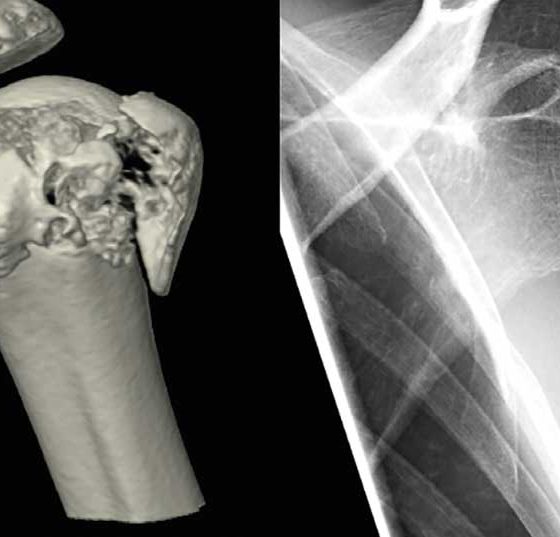

• Sportverletzungen des Schultergürtels

Aktuelles Fachwissen für den Hausarzt

Schulterverletzungen gehören zu den häufigen Sportverletzungen und zeigen ein breites Spektrum. Eine korrekte klinische und bildgebende Abklärung hilft, strukturelle Schäden zu erfassen und entsprechende therapeutische Mass­nahmen einzuleiten. Häufig ist es...…

• Die Schulter im Wintersport

Gefahren auf der Piste

«Alles fährt Ski» hiess 1963 ein Schlager von Vico Torriani, den die ­ganze Schweiz anstimmte. Die Zeiten haben sich leicht geändert, aber nach wie vor rufen die verschiedenen Schneesportarten viele...…